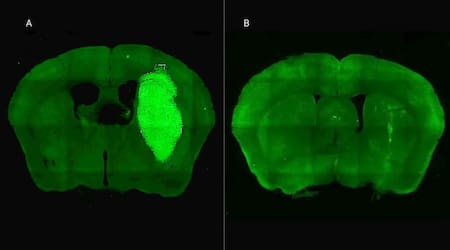

Además, P60 tuvo efectos antitumorales directos, reduciendo la viabilidad y la migración de las células de glioblastoma e inhibiendo la proliferación de células endoteliales que son clave para la progresión del tumor. Para evaluar estos efectos, los autores del estudio utilizaron una variedad de modelos celulares murinos (de roedor) y humanos. “En particular, los cultivos derivados de biopsias de pacientes con glioblastoma desarrollados por nuestro colaborador Guillermo Videla Richardson, del Instituto FLENI, son muy útiles para representar la heterogeneidad de estos tumores”, indicó Candolfi.